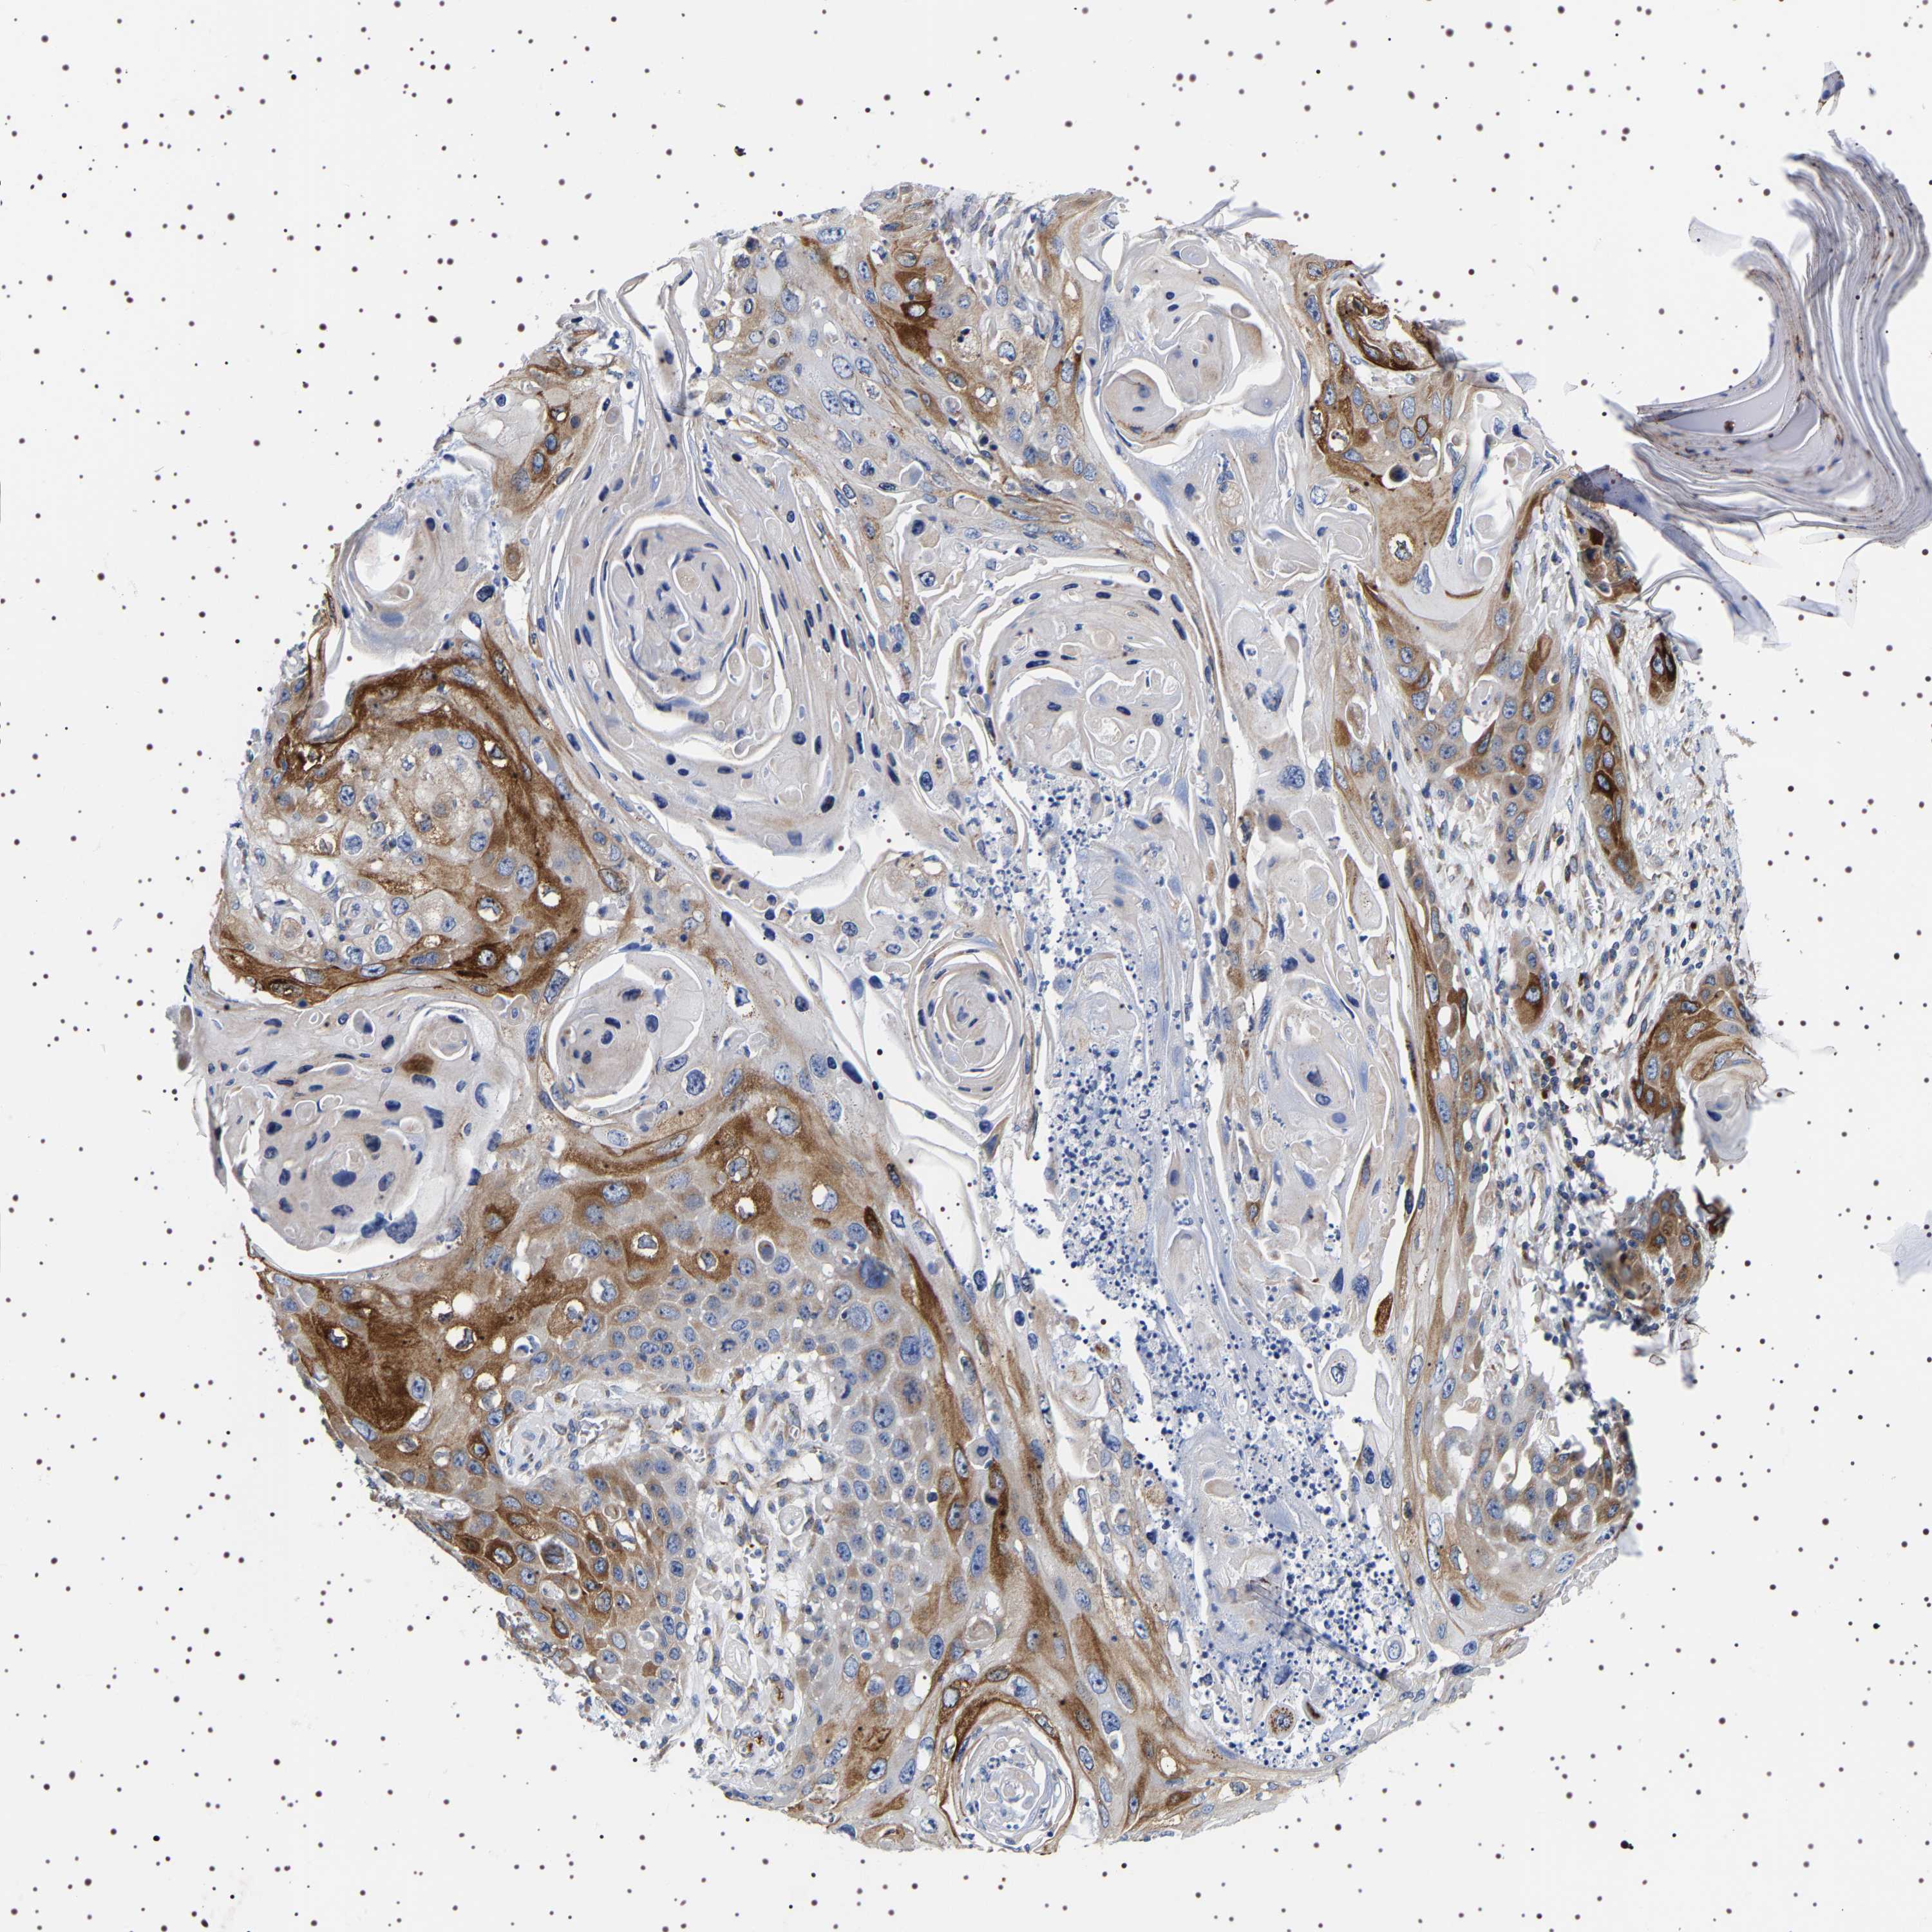

SKIN CANCER - Protein expressioni

A mouse-over function shows sample information and annotation data. Click on an image to view it in a full screen mode. Samples can be filtered based on level of antibody staining by selecting one or several of the following categories: high, medium, low and not detected. The assay and annotation is described here.

Each image is clickable and will lead to virtual microscopy that enables deeper exploration of all samples and also displays staining intensity scores, fraction scores and subcellular localization as well as patient and tissue information for each sample.

Antibody HPA018038

Staining

High

Medium

Low

Not detected

Intensity

Strong

Moderate

Weak

Negative

Quantity

>75%

75%-25%

<25%

None

Location

Nuclear

Cytoplasmic/membranous

Cytoplasmic/membranous,nuclear

Squamous cell carcinoma in situ, NOS

Squamous cell carcinoma, NOS

Squamous cell carcinoma, metastatic, NOS

Basal cell carcinoma